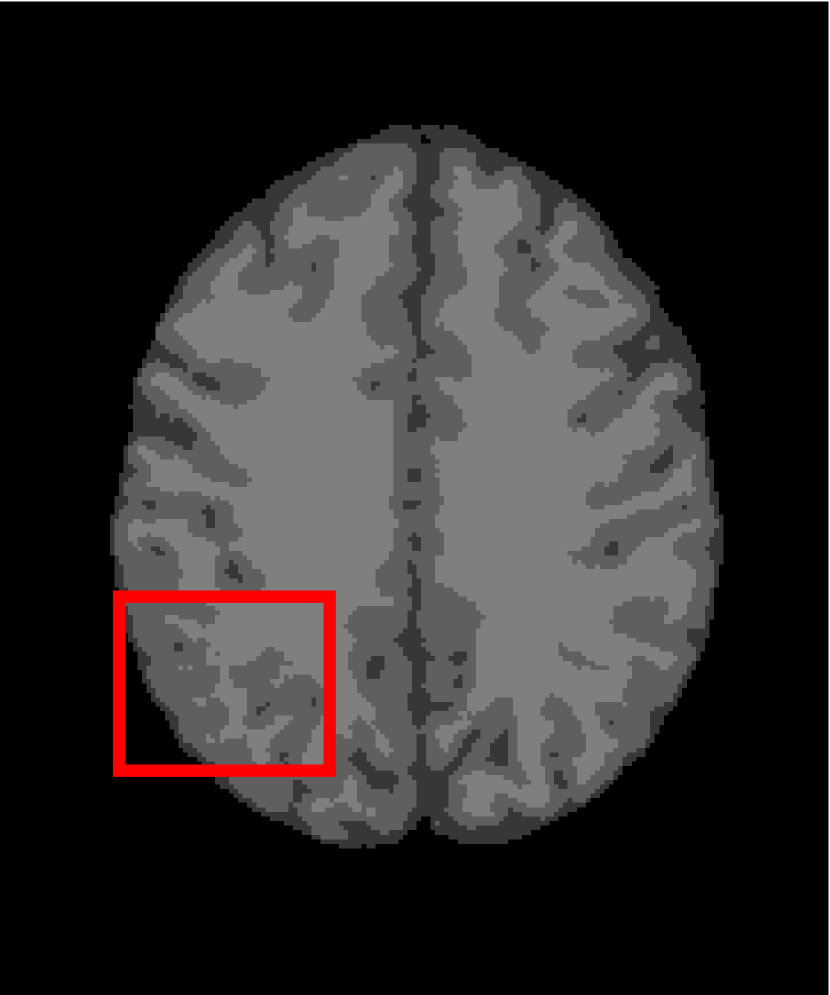

In the second experiments, we segment two medical images coming from a simulated brain database (BrianWeb): http://www.bic.mni.mcgill.ca/brainweb/. The two images are generated by T1 modality with slice thickness of 1mm resolution, 9% noise and 20% intensity non-uniformity. Here, the two images are represented two slices in the axial plane with the sequence of 100 and 110. Moreover, there are golden standard segmentations in the dataset. We set the numbers of clusters to 4. The visual comparisons are illustrated in Figs. 6 and 7.

Figure 6: Segmentation results for the first medical image. From (a) to (l): ground truth, noisy image and results of FCM_S1, FCM_S2, FGFCM, FLICM, KWFLICM, ARKFCM, FRFCM, WFCM, DSFCM_N, and LRFCM.

By focusing on the marked red square in Figs. 6 and 7, we easily find that FCM_S1, FCM_S2, FGFCM and ARKFCM are sensitive to noise. FLICM and KWFLICM are vulnerable to severe intensity inhomogeneity. FRFCM brings overly smooth results due to the use of gray level histograms. WFCM and DSFCM_N cause several contours to change. However, LRFCM acquires clear contours and suppresses noise adequately. Moreover, we find that the segmentation result of LRFCM is closer to ground truth.